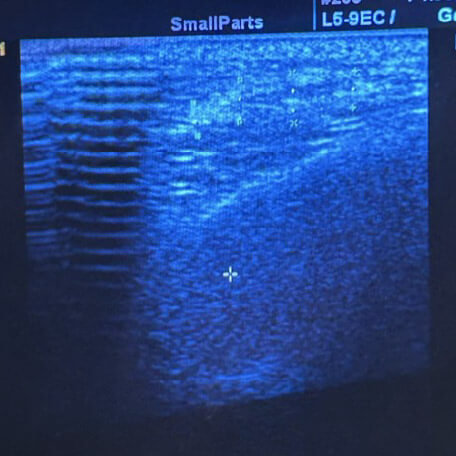

5.不可吸收物質

超音波:

中間不均勻的團塊,外圈是一圈亮白的膜;旁邊的纖維隔變粗,暗示慢性發炎的結果。

困擾:

材料不會被身體吸收,可能聚成團,身體會包起來(像小型「夾膜」);時間久了可能位移、下滑,還會反覆發炎。

處理:

先把能流動的不可吸收物質的部分引流掉 ,用消疤針把外面的「膜」和硬化區鬆開,看剩多少、臉型需要,再做顯微抽吸調整